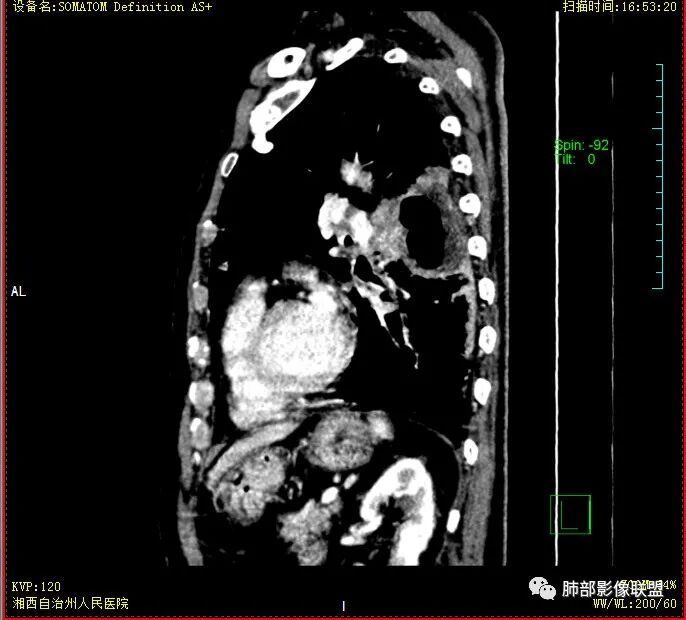

晨读:老年男性患者,痰中带血伴间断发热2周,体温39.4℃,白细胞、中性粒细胞,CRP增高,Tspot阳性,胸部CT:双肺病变,左肺下叶背段大片实变密度影,边界模糊,内部见空洞形成,空洞内壁总体光滑,有气液平,增强扫描轻度不均匀强化,一月后复查空洞消失,实变影吸收减少,考虑感染性病变,结核伴肺脓肿。

老年慢性长期吸烟,痰中带血伴发高热。左下肺大片不均质实变里可见一含气液平厚壁空洞,内壁有坏死物残留,增强可空洞壁明显强化轮廓显示清晰,空洞位于肺门侧,近端支气管壁不规则增厚。两肺散在斑片状影,并见小树芽。18号复查肺窗空洞显示不清,20号用了俯卧位扫描,液体向下流动空洞又显示出来了。左下肺病灶有变小,还是考虑感染性病变,结核合并感染,鉴别鳞癌。

双肺多发结节影,树芽征,小叶中心分布,左肺下叶不规则空洞,洞内壁光滑,见液平,洞壁似与支气管相通,增强扫描明显强化,可见血管造影征。三周左右复查空洞明显缩小。

双肺多发点片、索条斑条灶,见多发树丫征,左下肺大片不均质实变,内见一含气液平厚壁空洞,壁厚,内壁有坏死物残留,增强可空洞壁明显强化

,空洞位于肺门侧,近端支气管壁不规则增厚。

18号复查肺窗空洞显示不清,20号用了俯卧位扫描,液体向下流动空洞又显示出来了。

胸部CT:双肺多发小斑片、树芽、索条灶,左下肺大片不均质实变,远肺门侧厚壁空洞,气液平,内壁有坏死物残留,增强可空洞壁不均匀强化,近端支气管壁不规则增厚堵塞,实变影内可见与洞壁平行支气管。抗炎3周有缩小。

3.注意到左肺下叶空洞性病灶,腔壁厚度不均,环形强化较为明显,壁间支气管血管影走行,腔内液气平面,这通常见于感染性病灶,如脓肿,经治疗病灶吸收也高度支持病灶主体成分为脓肿。